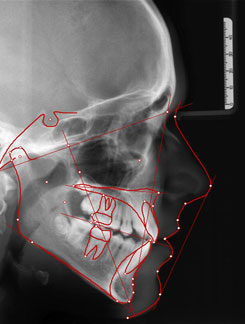

Die seitliche Schädelaufnahme (FRS) ziehen wir zur Analyse der Einlagerung von Ober- und Unterkiefer in den Gesichtsschädel, der Wachstumsrichtung und des Neigungswinkels der Schneidezähne heran.